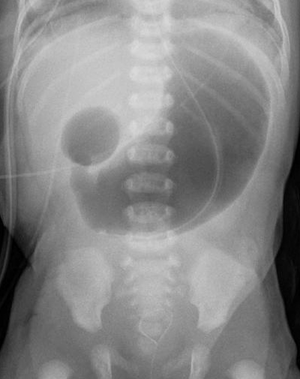

| Radiograph with double bubble sign indicating duodenal atresia | |

| Diagnostic method | Before birth: Ultrasound[1] After birth: X-ray[1] |

If not diagnosed in utero, infants with intestinal atresia are typically diagnosed at day 1 or day 2 after presenting with eating problems, vomiting, and/or failure to have a bowel movement.[3] Diagnosis can be confirmed with an X-ray, and typically followed with an upper gastrointestinal series, lower gastrointestinal series, and ultrasound.[6][3]